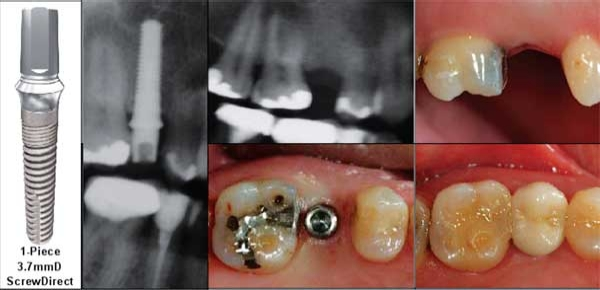

The replacement of a single missing tooth with a root-form dental implant is a relatively simple surgical procedure that can be performed by GPs. Many GPs are initiated to implant dentistry by placing one-piece mini-implants less than 3mm in diameter using a flapless procedure primarily for stabilizing a complete lower denture. These implants are not approved by the FDA for permanent tooth replacement. These mini-implants are not well suited for replacing a single missing tooth. They lack strength and surface area to withstand functional loads and do not offer an adequate diameter to create an esthetic emergence profile. Implant Direct offers the ScrewDirect™ 3.0mmD one-piece implant that flares to 3.7mmD above the bone, providing a straight abutment with a shoulder well suited for cementation of a single tooth restoration. This implant also has a retentive groove just above the 45 degree shoulder, and is provided with a snap-on comfort cap for temporary coverage and a snap-on transfer for an abutment level impression. All of Implant Direct’s one- and two-piece implants duplicate the surgical protocol developed by the author a decade ago to optimize initial stability in soft bone. This is accomplished by inserting a slightly tapered implant into a socket prepared with straight drills. Increased initial stability has proven critical for immediate load of free-standing, single tooth replacements, whether into an extraction socket or a healed edentulous area. The use of a 35Ncm torque wrench is generally accepted to be the quantitative way of determining whether an implant is capable of supporting an abutment with a temporary crown immediately following insertion. Splinting multiple implants that have achieved this level of initial stability has allowed the development of Teeth-in-1Day™ procedures for immediate function of implant supported, detachable prosthesis in edentulous jaws (see Article 2 in this series). The decision to place an implant without laying a flap depends on the clinician’s ability to visualize the ridge width in order to determine adequate bone to support the implant without the need for bone grafting. This is accomplished by probing or by the use of a CT scan. Laying a flap allows better visualization and affords the opportunity to do bone grafting or ridge splitting.

Implant Direct’s two-piece, bone-level implants are provided on a fixture-mount insertion tool that serves as a transfer and can be shortened for use as a snap-on or preparable abutment. The fixture-mounts of the Screw-Plant™ and RePlus™ Implants, when shortened, provide an abutment that duplicates the head of the ScrewDirect™ one-piece implant. The fixture-mounts of the Legacy3™ and ReActive™ Implants, when shortened, provide an abutment that can be modified to a 12 degree angle for esthetics and parallelism Providing these components free with the implants, not only reduces costs but also simplifies inventory, eliminating the need to order additional components.